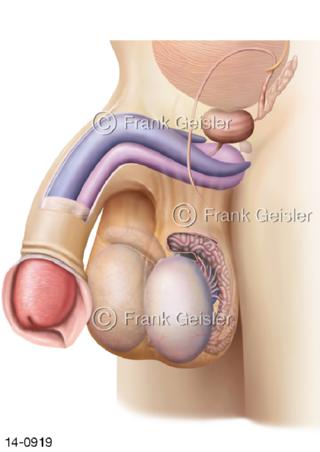

Bildergalerie Urogenitalsystem

Bilder zum Urogenitalsystem mit Urogenitalorgane, Urogenitaltrakt, zum Harn- und Geschlechtsapparat, Harnorgane und Geschlechtsorgane, Organe der Harnwege und der Fortpflanzung, Harnorgane und Geschlechtsorgane im männlichen und weiblichen Urogenitalsystem